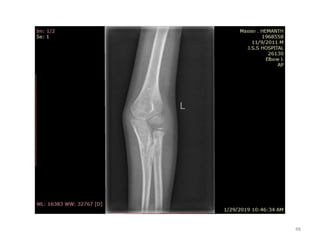

Elbow joint

• Secondary ossification Centres : (3 bones; 6 Ocs)

Capitulum (C) - appearance - 1 year of life

Head of Radius (R)– appearance -4 to 5 years

Medial Epicondyle (ME)

Appearance – 5 to 6 years

Fusion – 16 to 17 years

Trochlea (T) – appearance – 9 to 11 years

Olecranon Process of Ulna (OP)

Appearance - 8 to 9 years

Fusion- 16-17 years

Lateral Epicondyle(LE) – 11 to 12 years

Conjoint (Composite)Epiphysis (CE) [fusion of C+T+LE]

Formation – 14 to 16 years

Fusion – 16-17 years

Note: Fusion of O.Centres at elbow joint is 16-17 years in male, 15-16 years in female

All OCs Appeared and fused (>16-17 years)